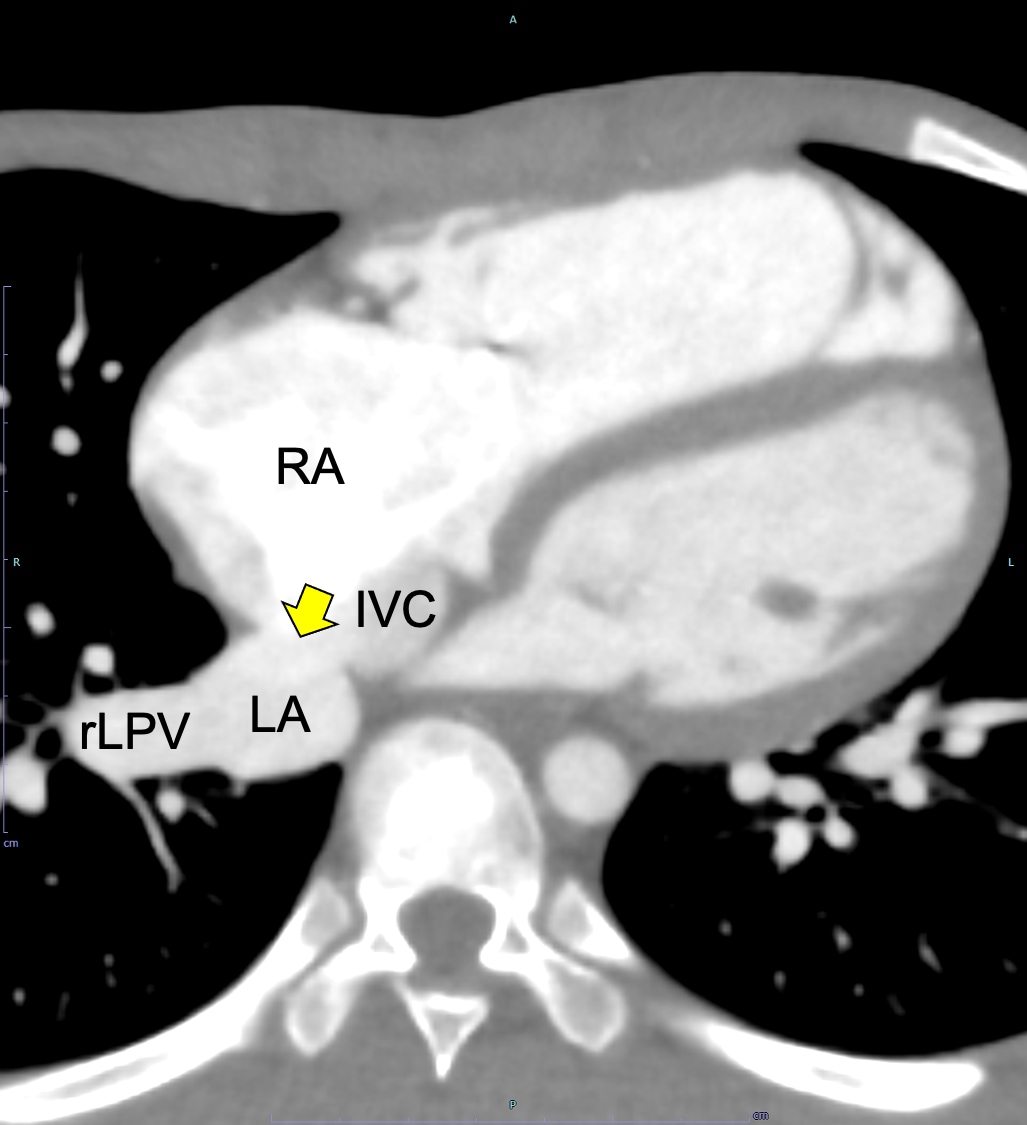

図1.心電図同期造影CT水平断(動脈相、欠損孔レベル)

下大静脈付近で左右の心房間に欠損孔(矢印)を認める。RA: 右心房、 LA:左心房、rLPV: 右下肺静脈、IVC: 下大静脈